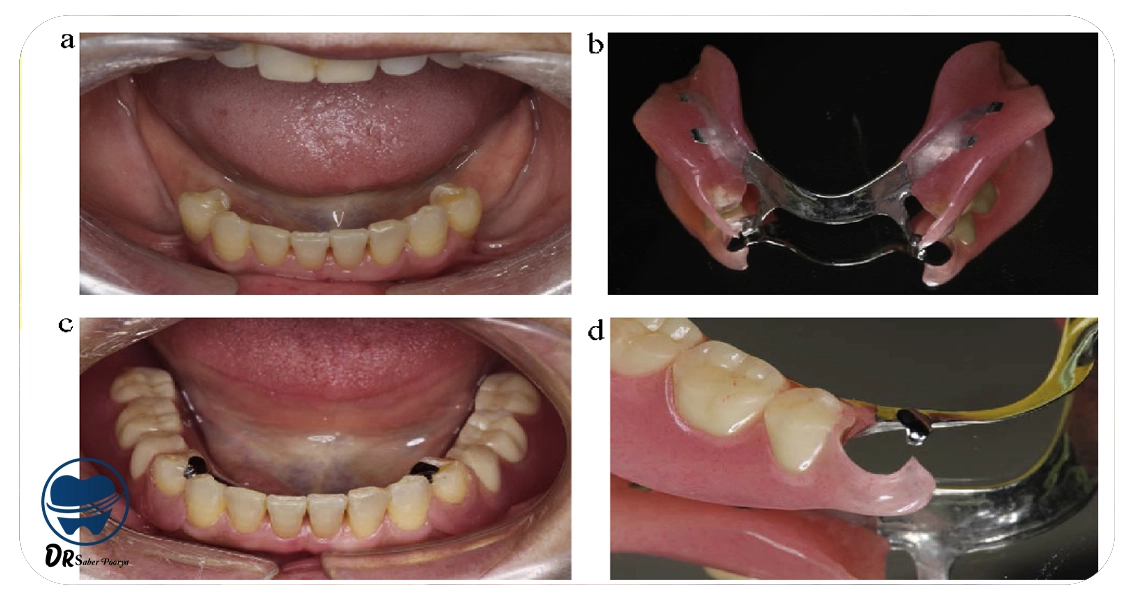

دندان مصنوعی متحرک در مشهد

دندان مصنوعی متحرک را میتوان هنگام نیاز از دهان خارج و دوباره جایگزاری کرد و به همین دلیل گزینهای راحتتر و معمولاً اقتصادیتر برای جبران دندانهای از دسترفته است.

این نوع دندانها در مشهد بهعنوان راهکاری انعطافپذیر و قابل دسترس شناخته میشوند.

انواع دندانهای مصنوعی متحرک

دندان مصنوعی پارسیل (Partial Denture): زمانیکه تنها چند دندان افتاده و بقیه سالماند، از این نوع دندان استفاده میشود.

با کمک گیرههای مخصوص به دندانهای طبیعی متصل شده و هم زیبایی و هم عملکرد جویدن را بهبود میدهد. این روش در مواقعی که امکان استفاده از دندان ثابت وجود ندارد، پیشنهاد میشود.